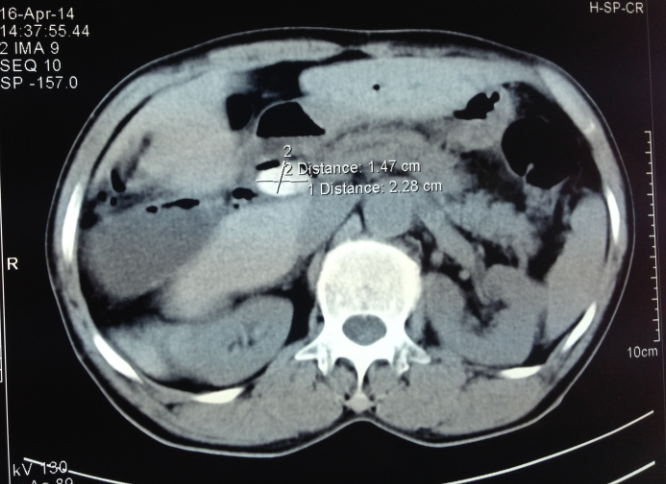

3.3.4. Chụp cắt lớp vi tính (CLVT)

Chụp CLVT là phương pháp chẩn đoán hình ảnh không gây sang chấn, có giá trị trong chẩn đoán sỏi đường mật tốt hơn nhiều so với siêu âm, rất tốt trong phát hiện sỏi canxi, có tỷ lệ chính xác cao. Tuy nhiên, CLVT cũng gây hại cho bệnh nhân bởi tia X (nhất là phụ nữ có thai) và thuốc cản quang có thể gây dị ứng, chi phí tốn kém, chỉ định còn hạn chế.

Chụp CT để xác định sỏi có độ chính xác 65-90%, chẩn đoán vị trí sỏi 85-88%. Độ nhạy của CT trong chẩn đoán sỏi mật từ 50-90% [5].

Hình 6. Hình ảnh sỏi ống mật chủ trên CLVT [5]